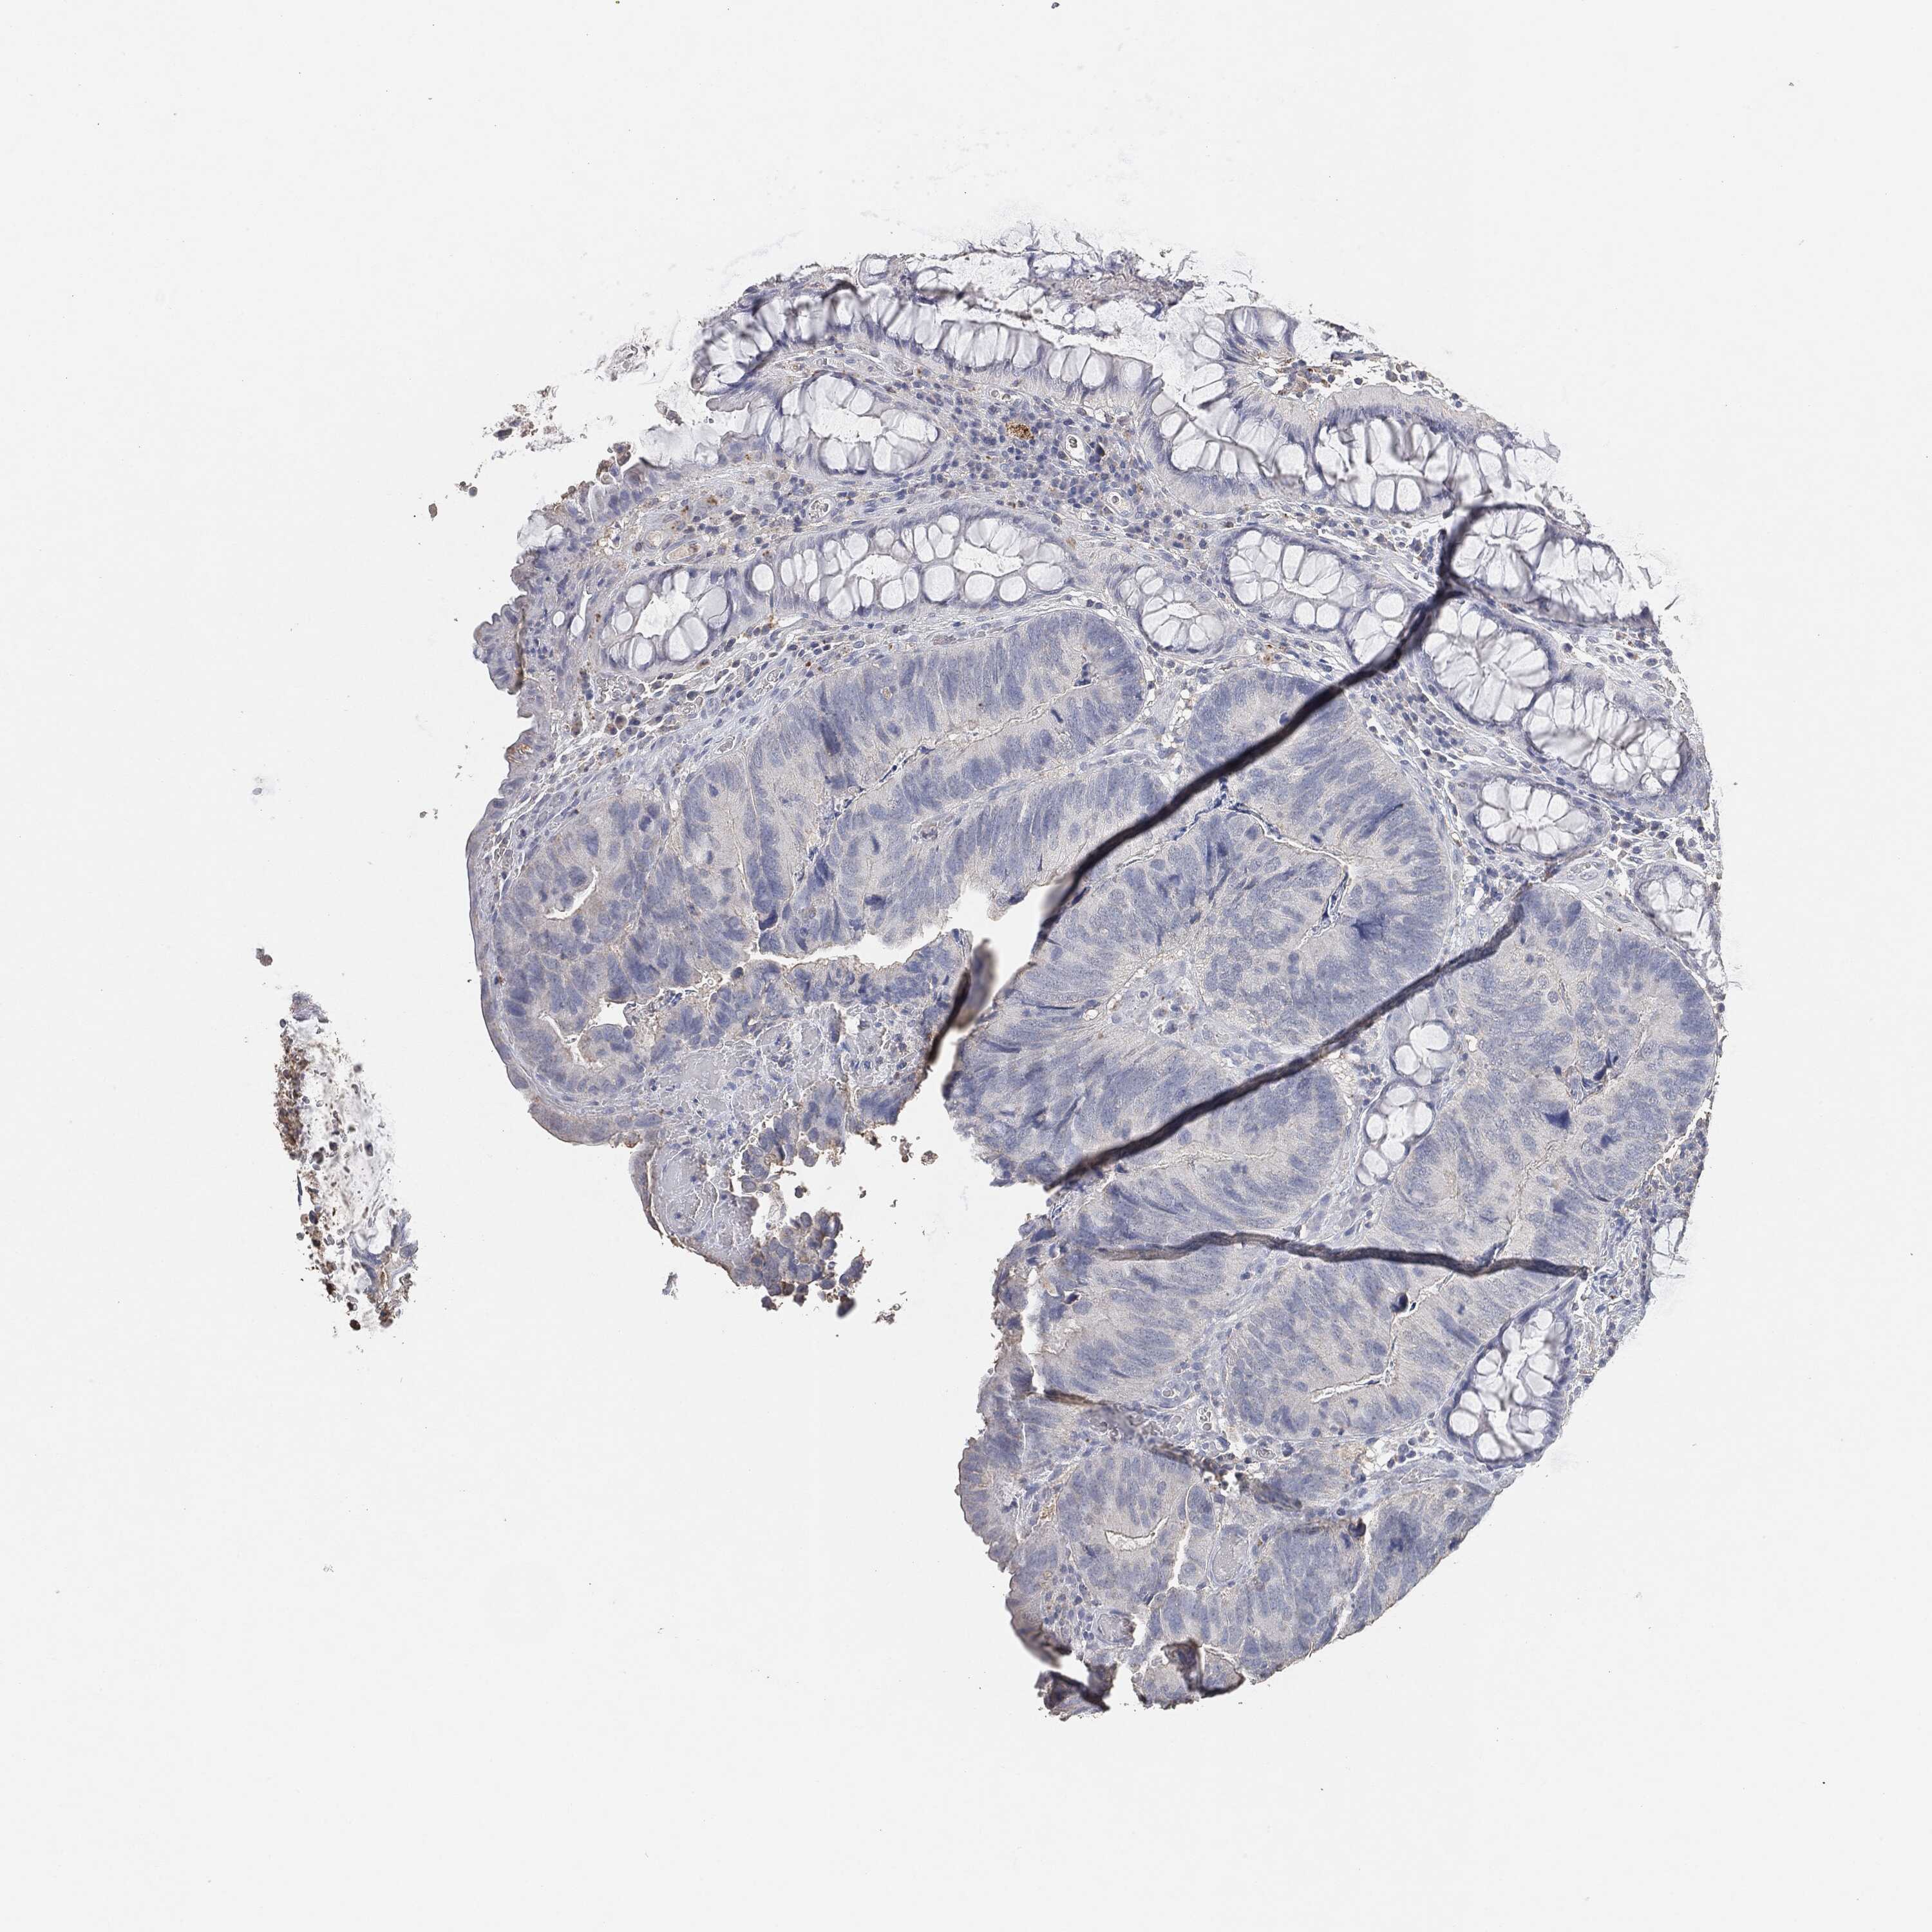

CANCER COLORECTAL CANCER Show tissue menu

Colorectal cancer

Human cancer

Colon adenocarcinoma